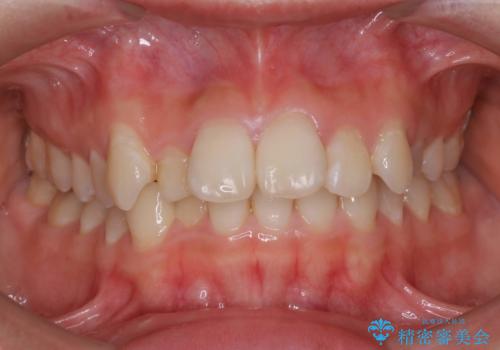

ハーフリンガル矯正 抜歯をして前歯を下げる

上顎の抜歯により上の前歯の位置を大幅に後ろに下げることができます。

奥歯の位置関係など、様々な要素を加味し、適応を判断する必要があります。